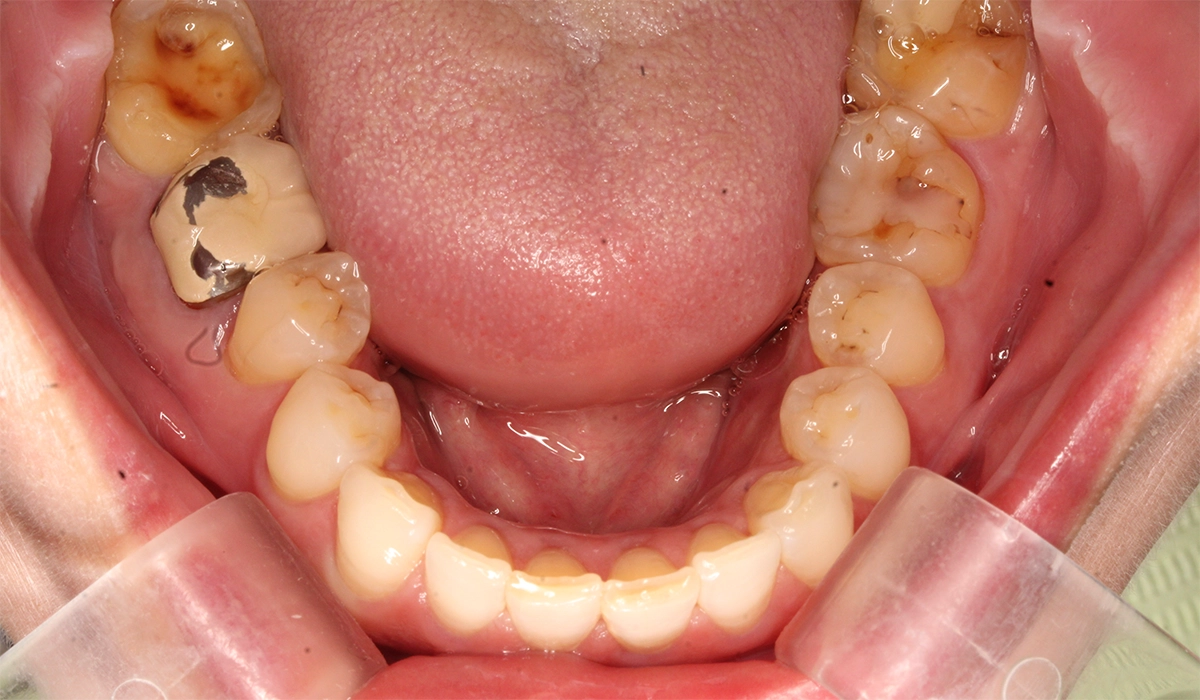

術前:下顎